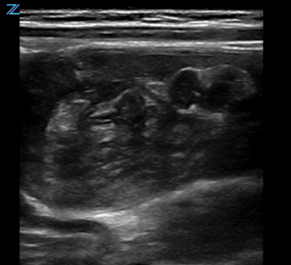

Classically, intussusception manifests in the transverse orientation as a ‘target sign’ or ‘donut sign’ (Figure 1) representing layers of intestine within the intestine. In the longitudinal orientation, the layers of intestine appear as a ‘pitchfork’ or ‘submarine sandwich’ (Figure 2). These findings are most commonly seen in the right lower quadrant for ileocolic intussusception, which is the most common type of intussusception. Small bowel intussusceptions can be differentiated by their size, which are often ≤3 cm.5 While small bowel intussusceptions often spontaneously reduce, if symptoms and findings persist, computed tomography (CT) may be necessary to determine management. POCUS is useful in differentiating variants of intussusception that range from a surgical emergency to a transient source of abdominal pain allowing clinicians to better manage these patients.6

Figure 1. Target Sign on cross-sectional image of intussusception